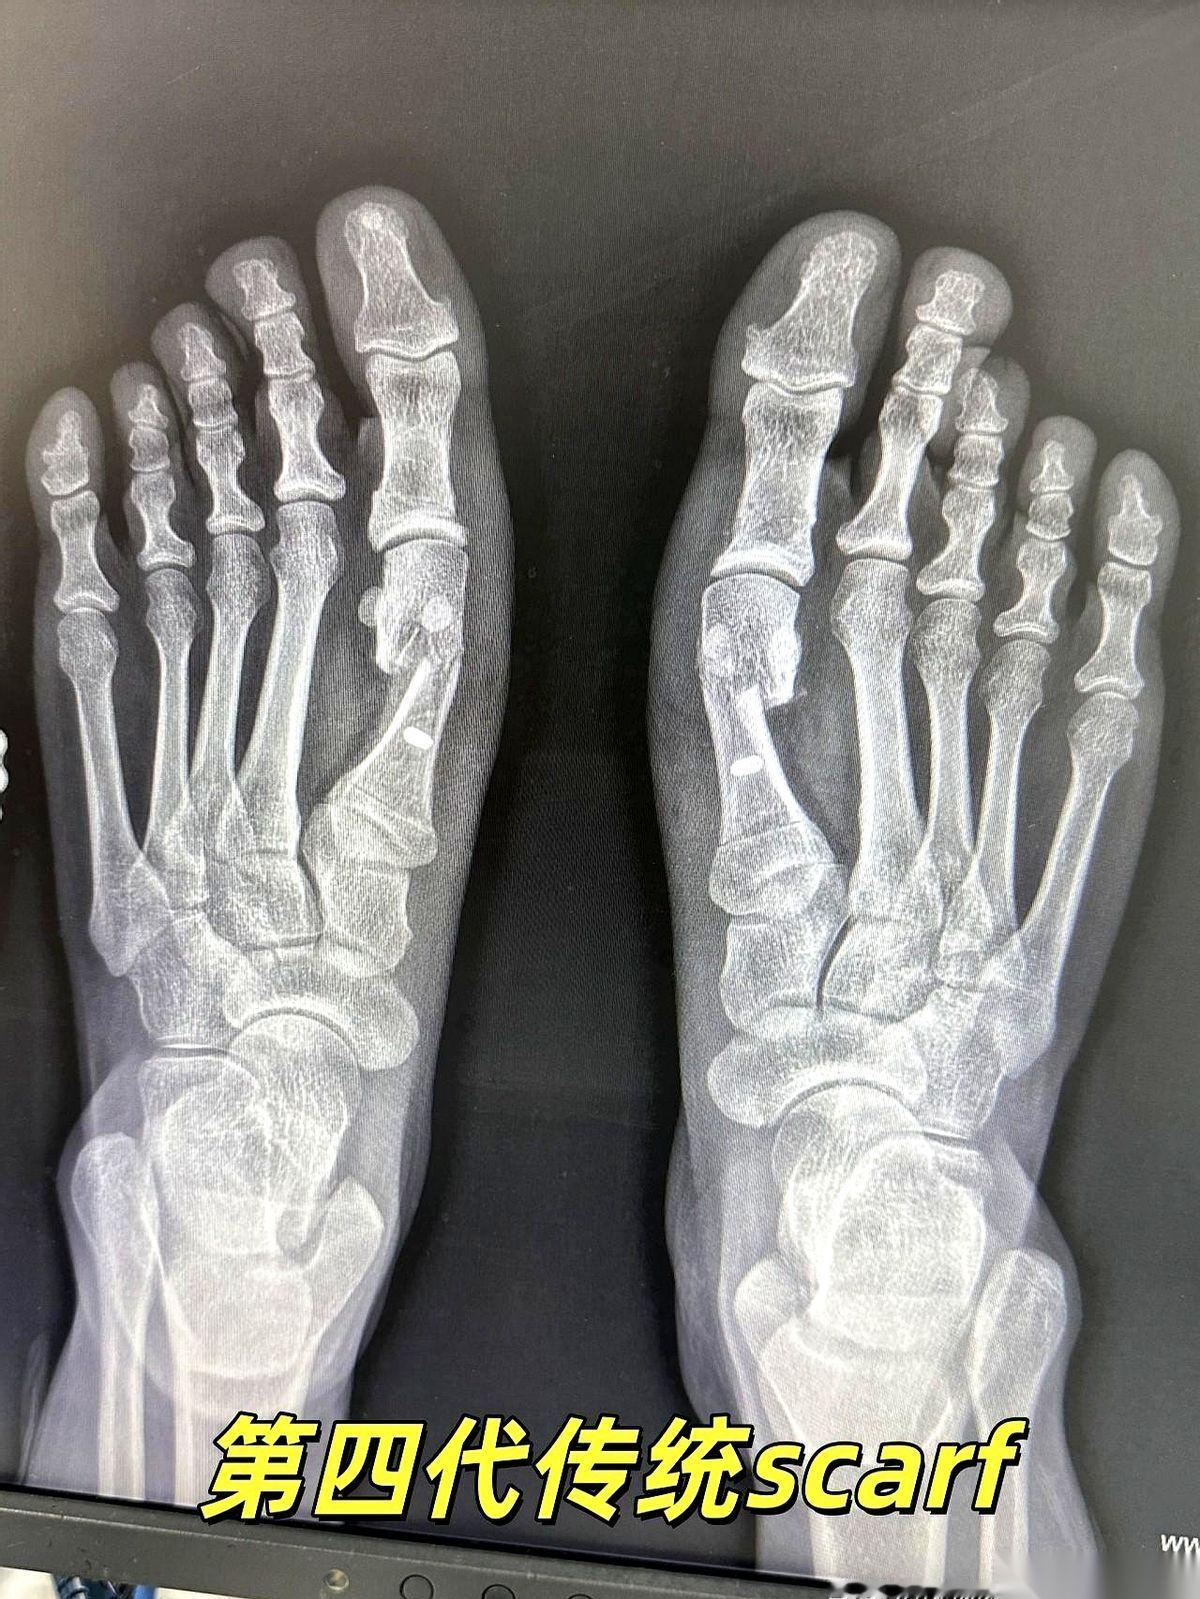

我跟你说,最狠的营销,就是把一个明明需要“伤筋动骨一百天”的事儿,包装成“随做随走”的下午茶。 拇外翻手术就是个典型的例子。 广告里,美女穿着高跟鞋,优雅地走出诊所,好像只是去修了个指甲。 但现实呢?现实是骨头被截断了,是真刀真枪地在你脚上动了刀子。 然后有人信了,真的去了。术后疼得龇牙咧嘴,脚肿得跟个馒头似的,跑去问医生。 医生云淡风轻一句:“挺好的,正常恢复。” 正常个鬼啊。 骨头断了,你拿什么固定?就靠外面绑个绷带? 这就好比房子的大梁歪了,你不用钢筋水泥去加固,反而在墙上贴了个“请勿靠近”的条子,指望它自己长结实? 做梦呢。 “不打钉”听起来好像多高级,多微创。 说白了,很多时候就是省事儿,但风险全留给了你。 骨头长歪了,畸形复发了,甚至得二次手术再遭一遍罪,这些广告里会说吗? 所以啊,别再被那些“不打钉、随做随走”的漂亮话给忽悠了。 下次你再咨询,就直接问那个最根本的问题: “医生,我这截断的骨头,您打算怎么让它稳稳当当地长好?” 看他怎么回答。 身体是自己的,不是试验田。任何手术,都得尊重最基本的生理规律。 捷径的尽头,往往是更远的路。